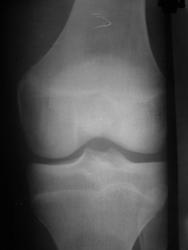

М.15лет. Жалобы на периодическую жгучую боль в L коленном суставе,после умеренной нагрузки, беспокоит 1мес. https://radiomed.ru/sites/default/files/styles/case_slider_image/public/user/15746/p4090030.jpg?itok=kvBtdL0b https://radiomed.ru/sites/default/files/styles/case_slider_image/public/user/15746/p4090031.jpg?itok=wUf85A5t ID:50918 Mon, 09/04/2012 - 17:48 #1 nelly Offline Last seen: 11 years 3 months ago Joined: 11.07.2011 - 19:19 Posts: 328 мне видится какой-то участок разряжения костной ткани в н3 диафиза БК..,не знаю как стрелочки ставить,а то отметила бы,а суставе артроз похоже имеется Mon, 09/04/2012 - 19:51 #2 ДокRg Offline Last seen: 12 years 6 months ago Joined: 30.03.2011 - 20:05 Posts: 105 nelly wrote: мне видится какой-то участок разряжения костной ткани в н3 диафиза БК..,не знаю как стрелочки ставить,а то отметила бы,а суставе артроз похоже имеется Я бы назвал этот участок разряжения - пятном Лудлофа( норма). А вот для исключения болезни Осгуд-Шляттера сделал бы снимки б/берцовых костей обеих ног с большим захватом. Mon, 09/04/2012 - 20:40 #3 maker4ik Offline Last seen: 8 years 9 months ago Joined: 19.10.2011 - 17:49 Posts: 2682 ДокRg wrote: nelly wrote: мне видится какой-то участок разряжения костной ткани в н3 диафиза БК..,не знаю как стрелочки ставить,а то отметила бы,а суставе артроз похоже имеется Я бы назвал этот участок разряжения - пятном Лудлофа( норма). А вот для исключения болезни Осгуд-Шляттера сделал бы снимки б/берцовых костей обеих ног с большим захватом. Пятно Лудлофа в эпифизе находится, а nelly про н/3 диафиза говорит. Mon, 09/04/2012 - 20:56 #4 Любовь С. Offline Last seen: 9 years 8 months ago Joined: 23.12.2010 - 01:58 Posts: 2324 Переснять диафиз в 2 проекциях. "Предоставляя весь смысл и совершенство в распоряжение одного только Бога, вы избавляете себя от бездны хлопот." Джон Уитборн. Mon, 09/04/2012 - 21:00 #5 nelly Offline Last seen: 11 years 3 months ago Joined: 11.07.2011 - 19:19 Posts: 328 да,да,я именно про это пятно,которое maker4ik указал стрелкой. Mon, 09/04/2012 - 21:17 #6 И.Бондаренко Offline Last seen: 17 hours 14 min ago Joined: 13.09.2011 - 22:55 Posts: 9209 Есть незначительное снижение медиальной суставной щели. А так бы написал норму. Tue, 10/04/2012 - 03:23 #7 Демчев Валентин... Offline Last seen: 7 years 10 months ago Joined: 08.02.2011 - 15:40 Posts: 445 Никакой болезни Осгуда-Шлаттера здесь нет. Переснять диафиз в 2-х проекциях, опять какой- нибудь метафизарный корковый дефект.

мне видится какой-то участок разряжения костной ткани в н3 диафиза БК..,не знаю как стрелочки ставить,а то отметила бы,а суставе артроз похоже имеется

Пятно Лудлофа в эпифизе находится, а nelly про н/3 диафиза говорит.

Есть незначительное снижение медиальной суставной щели. А так бы написал норму.

Никакой болезни Осгуда-Шлаттера здесь нет. Переснять диафиз в 2-х проекциях, опять какой- нибудь метафизарный корковый дефект.